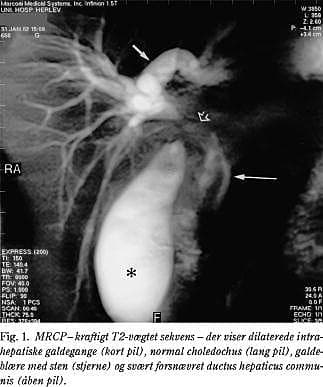

Pga. stigende leverenzymer blev der udført en MR-scanning med MR-cholangio-pankreatikografi (MRCP) fem dage efter UL-scanningen. MR-scanningen viste en snæver striktur på DHC (Fig. 1 ) pga. kompression fra bløddelsfylde i porta hepatis samt indkilet sten i collum. Der var betydelig intrahepatisk galdestase, men choledochus var normal. Galdeblæren indeholdt multiple sten og var omgivet af fri væske. En åben kolecystektomi bekræftede MR-diagnosen Mirizzis syndrom. Man fandt galdeblæren pusholdig med en sten indkilet i collum og omgivet af svære inflammatoriske forandringer, som forårsagede kompressionen af DHC. Via koledokotomi fandtes strikturen i DHC eftergivelig. Der var ingen fistel mellem galdeblæren og choledochus.

Hverken med CT eller UL-scanning kan man altid med sikkerhed diagnosticere Mirizzis syndrom (5). Med ERCP kan man se strikturen og nogle gange den indkilede sten, men metoden er invasiv og rummer risiko for komplikationer, og man kan ikke se det omgivende inflammatoriske infiltrat direkte. MRCP med kraftige T2-vægtede sekvenser er til gengæld en ikkeinvasiv, hurtig og smertefri teknik til synliggørelse af galdevejene. Regulære MR-snitbilleder viser ekstrabiliær patologi, som den inflammatoriske bløddelsfylde i ovennævnte sygehistorie. Mirizzis syndrom bør overvejes som årsag til intrahepatisk galdestase hos galdestenspatienter, og MR-scanning rummer mulighed for at stille denne diagnose.